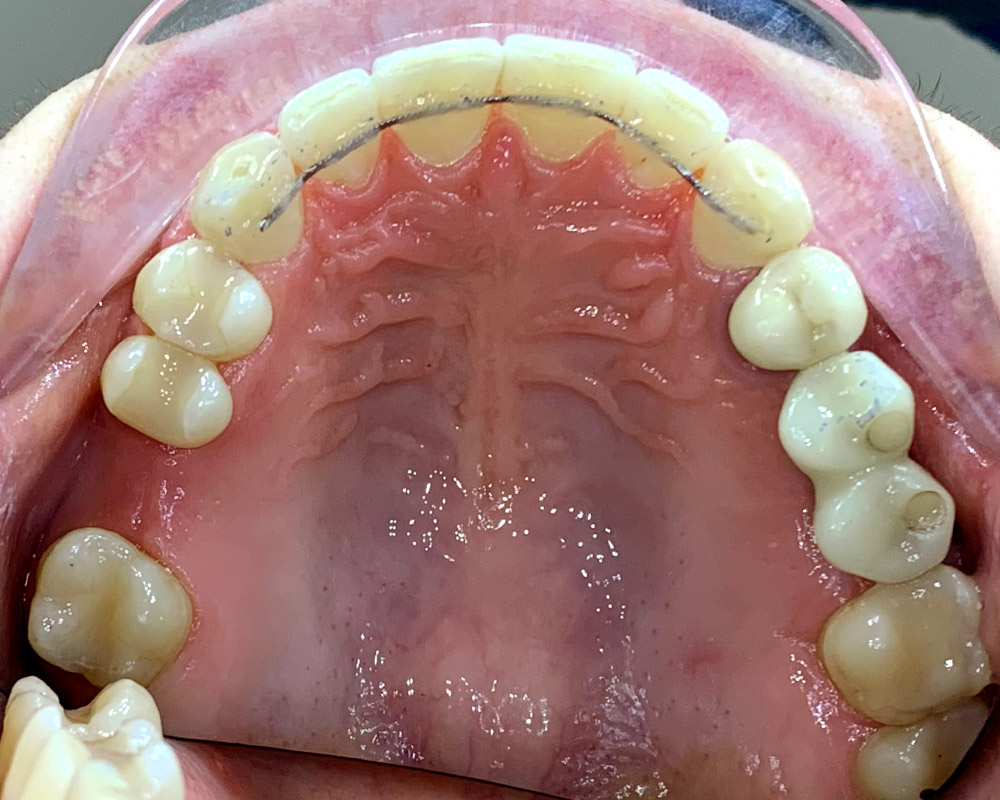

Кейс 23

Иванова Екатерина Сергеевна

Количество кап ВЧ 24

Количество кап НЧ 24

ДО

ПОСЛЕ